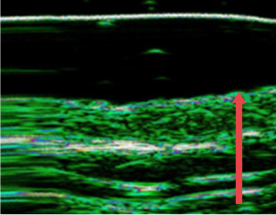

ปรับปรุงชั้นหนังแท้ของผิวหนังที่บางลงเนื่องจากความชรา การทำหัตถการผิวบ่อยๆ และการกระตุ้นจากภายนอก

ก่อนฉีด

หลังฉีด 4 เดือน

(ชั้นหนังแท้หนาขึ้น 12%)

หลังฉีด 7 เดือน

(ชั้นหนังแท้หนาขึ้น 27% )